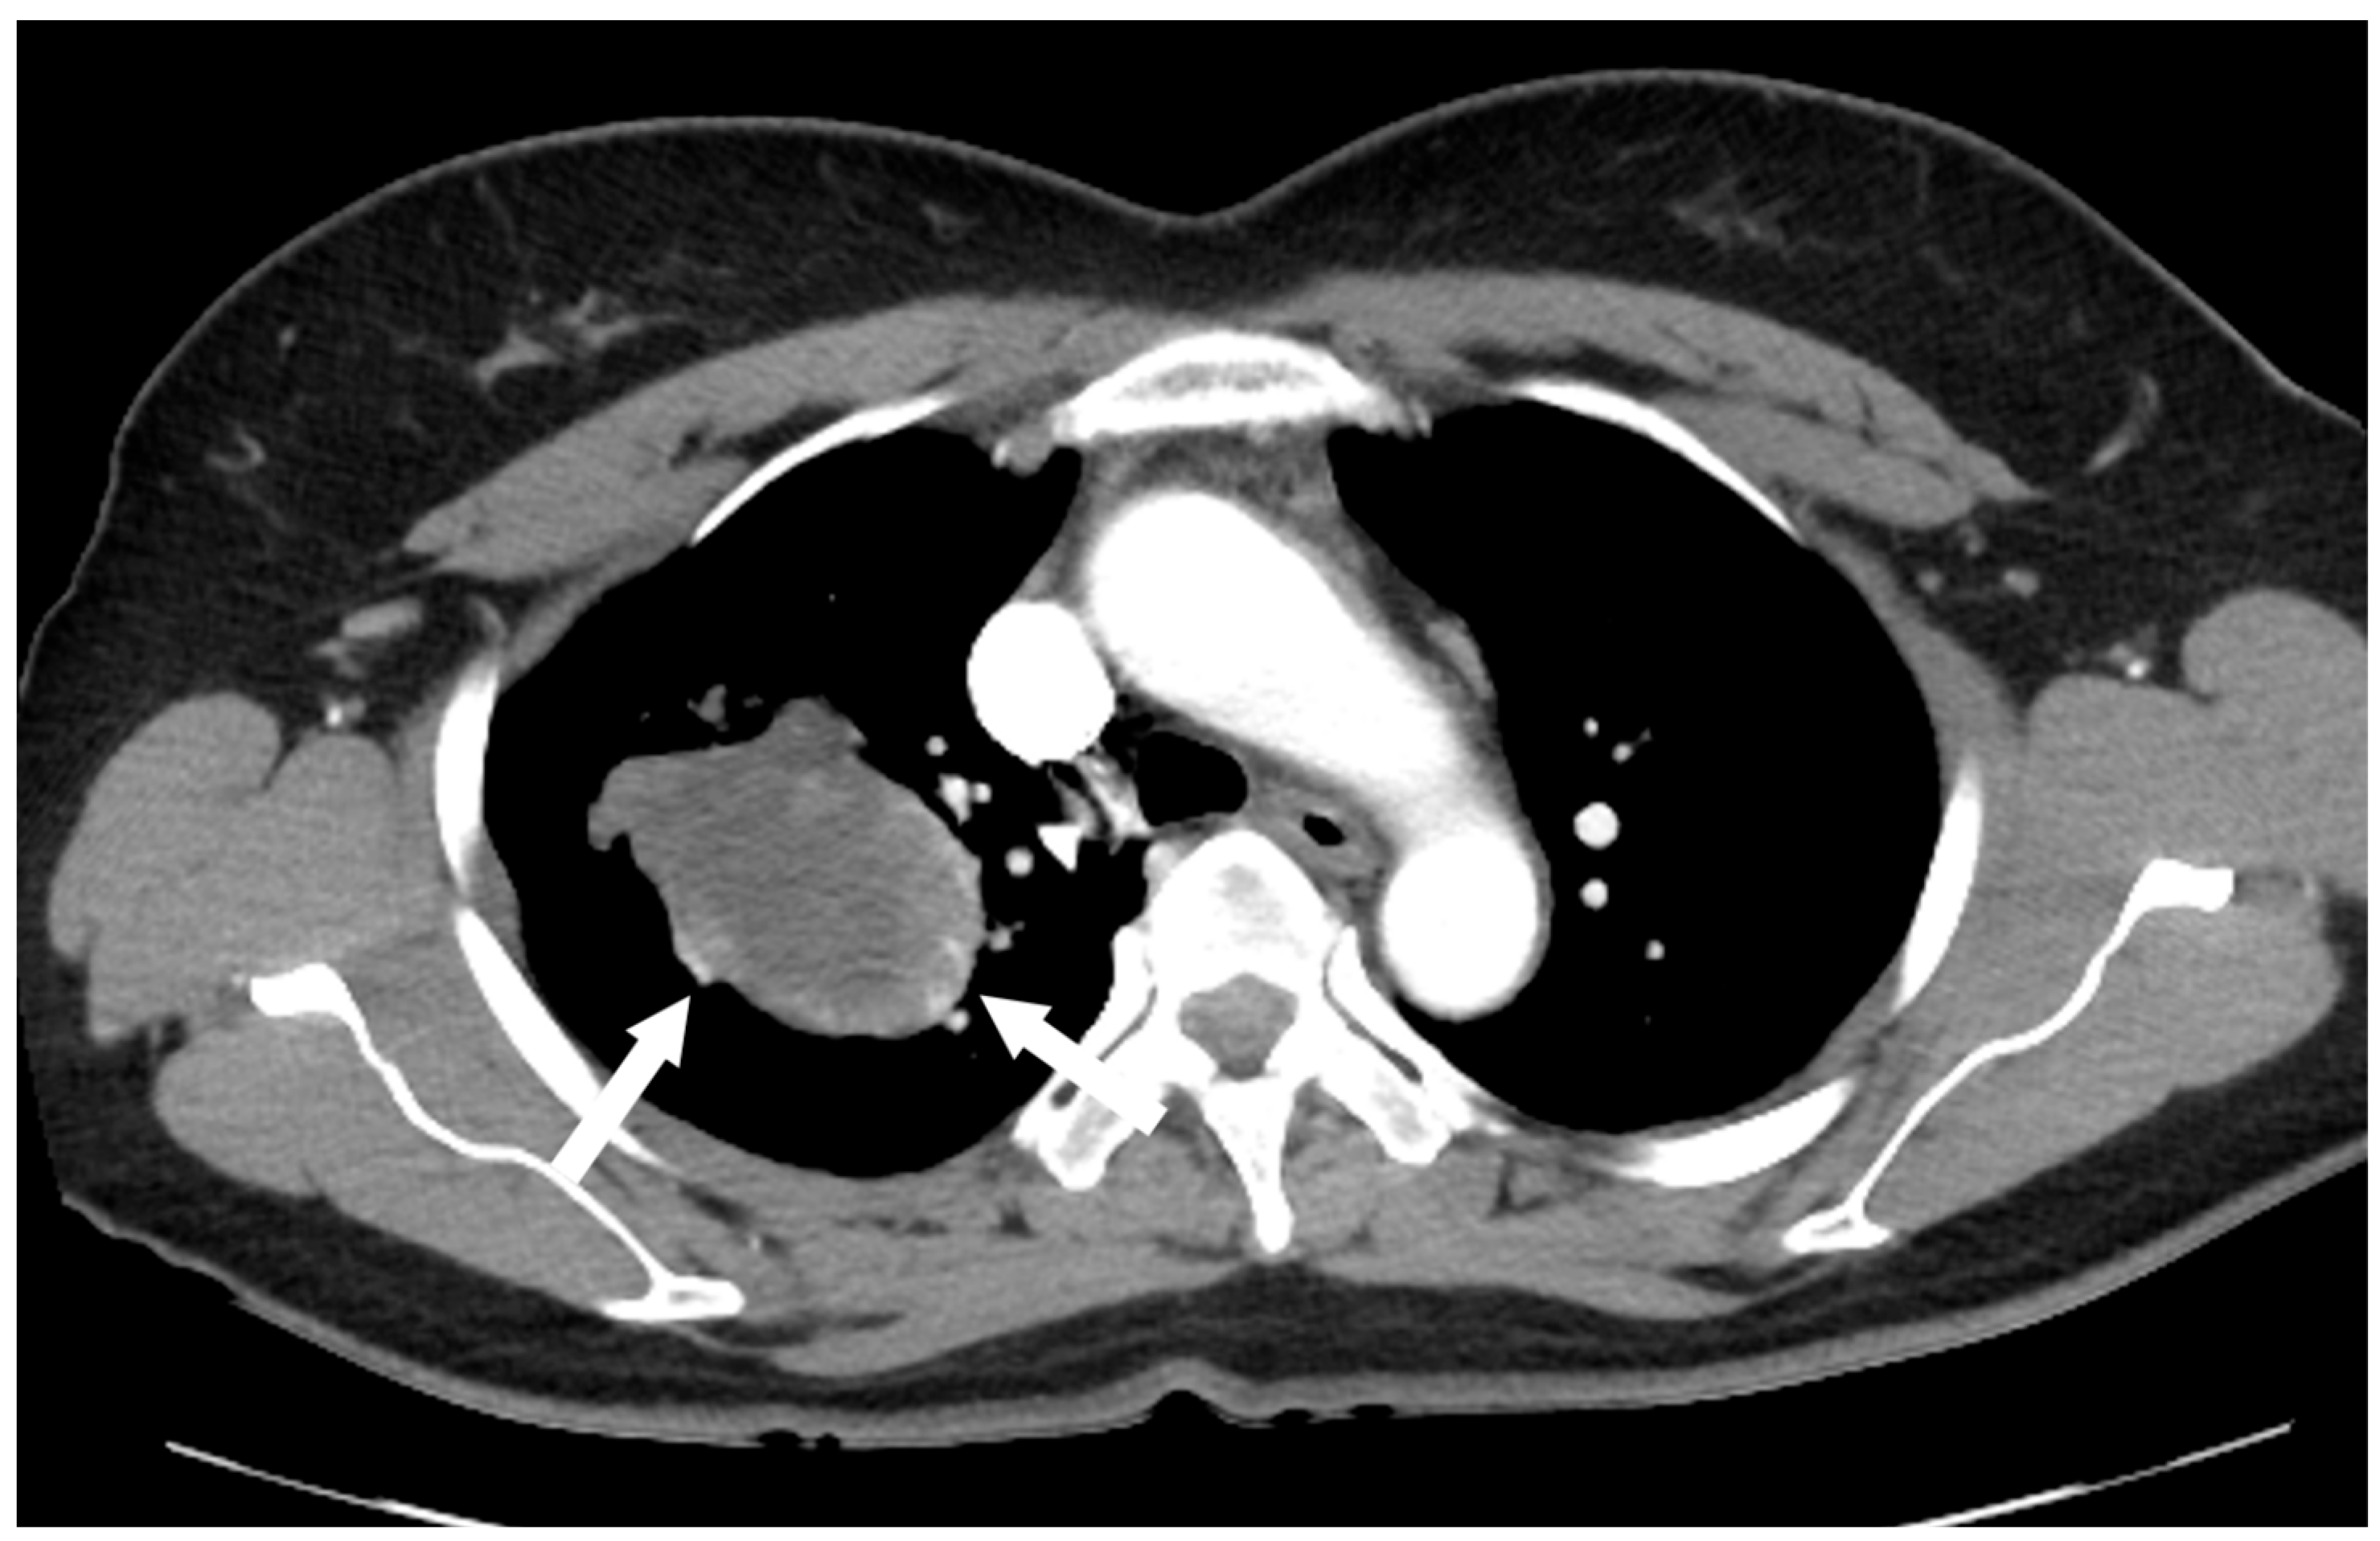

Figure 3.

Contrast-enhanced chest CT revealed a poorly enhancing mass resembling a cystic lesion, but with strong nodular or curvilinear enhancement along the periphery of the mass.